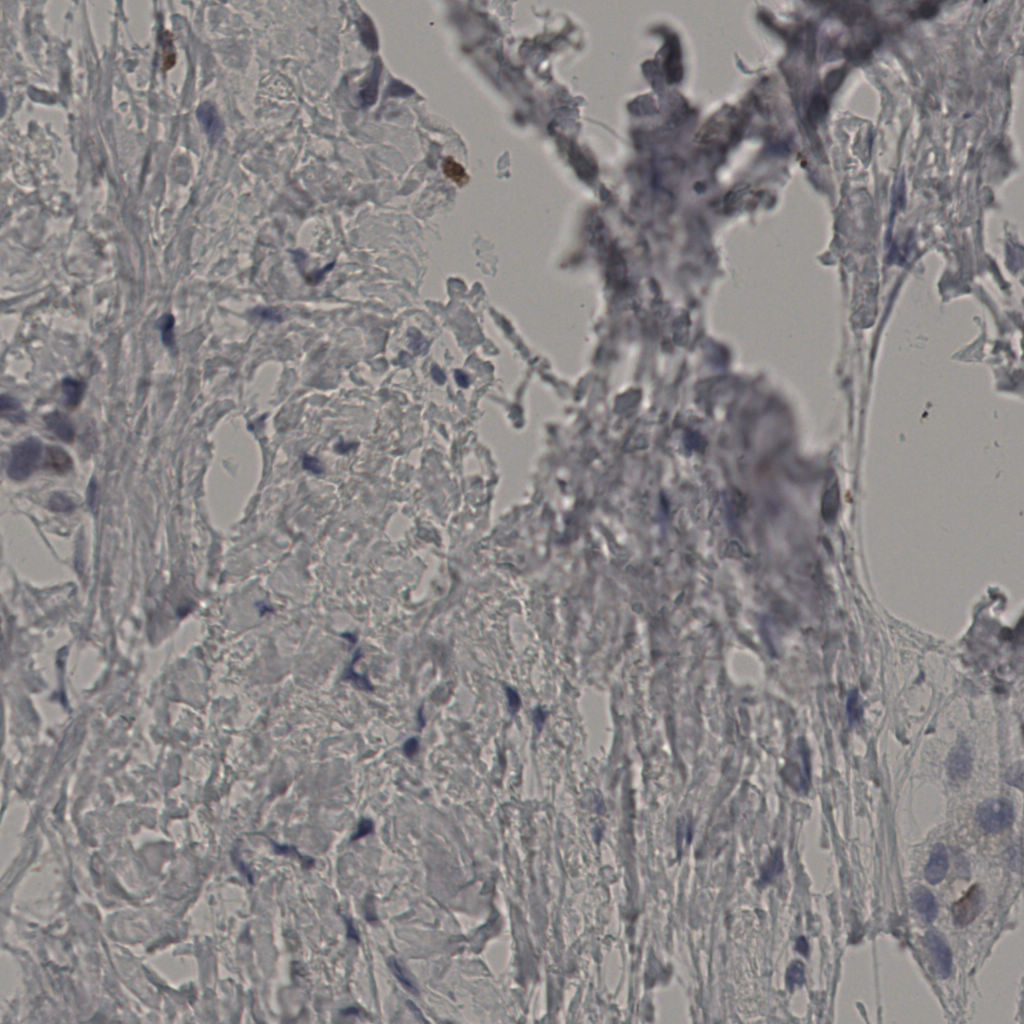

缩略图

标记后

标记前